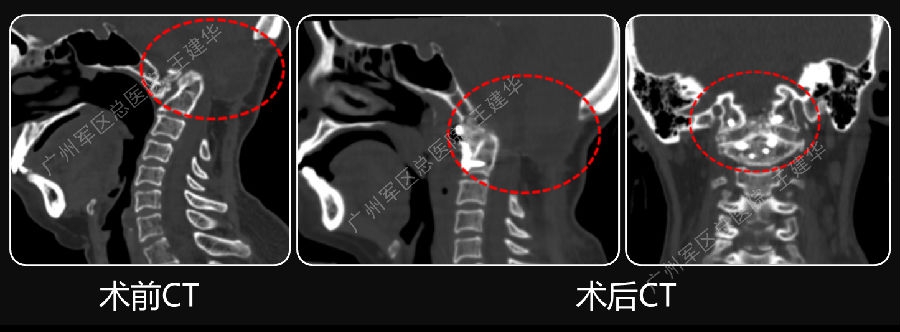

手术前后对比

手术后CT显示,陷入枕骨大孔的齿突获得下拉复位

术后MRI发现,患者的颅底凹陷,脊髓空洞和Chiari畸形均获改善